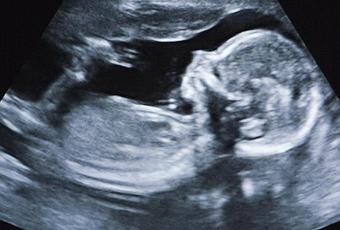

Les faits se sont déroulés au Chili, une femme âgée de 92 ans a découvert à son plus grand étonnement qu’elle portait dans son corps un fœtus momifié.

Lors d’un examen radiographique de routine après une chute, cette grand-mère chilienne de 92 ans portait un fœtus momifié pesant près de deux kilos depuis au moins 50 ans. Les faits ont été dévoilés par une source médicale en fin de semaine. Un médecin de San Antonio a déclaré sur une radio locale que cette découverte était totalement fortuite.

Pourquoi l’enfant s’est-il momifié ? Les raisons restent inconnues. La nonagénaire après cette découverte des plus étranges a pu regagner son domicile sans avoir subi aucune chirurgie. Cette femme était enceinte de sept mois lorsque le bébé s’est momifié à l’intérieur de son corps.